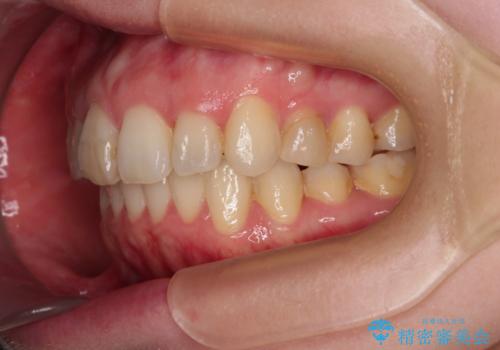

- 上顎前歯の突出感と、前歯のクロスバイトを気にして来院された患者様です。

前歯の叢生と口元の閉じにくさを気にして来院された患者様です。

奥歯の咬み合わせを見ると、上顎が下顎に対して相対的に前方にありました。

カリエール・ディスタライザーを用いたことで上顎前歯の突出感はスムーズに解消され、歯列不正は1年半ほどでほぼ改善することができました。